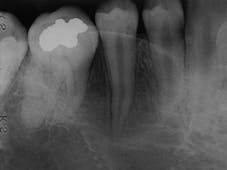

Case 2

Condensing Osteitis

1. Identify the most common location for condensing osteitis.

2. Identify the radiographic appearance of condensing osteitis.

3. Identify the treatment of choice for condensing osteitis.

4. Identify the true statement concerning condensing osteitis.